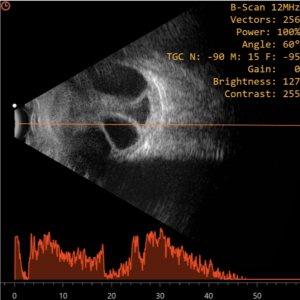

Conventional ophthalmic ultrasonography (USG) uses a probe that oscillates between 7.5 – 12 Mega Hertz. Diagnostic ophthalmic ultrasonography may employ either a unidirectional amplitude modulated (A scan), first reported in 1956 by Mundt and Hughes and the two-directional cross-sectional brightness (B scan) scan, introduced in ophthalmic practice by Baum and Greenwood in 1958. Frequently, both the A-scan and B-scan complement each other and are often used together.It is non-invasive, non-ionizing, inexpensive, and easily performed imaging technique. It is useful in detecting intraocular foreign bodies (IOFB) and outlining soft tissue abnormalities of the eye and orbit in presence of media opacity.[3] It is relatively contraindicated in the presence of open globe injury, to avoid further trauma and wound contamination. Thus, in case of a ruptured globe, it is highly recommended that primary closure should be performed prior to ultrasound examination. If ultrasound examination is performed prior to primary closure, it should be performed with caution to minimize possible trauma to the eye. Sterility is essential if the globe is open or a wound has been recently closed. The probes should be sterile, or they may be placed in sterile rubber sleeves.[4]

Vitreous

Vitreous hemorrhage is one of the commonest findings in patients with trauma. Recent mild hemorrhage is imaged as dots and short lines on B-scan, and as chain of low amplitude spikes on A-scan. With dense hemorrhage, more opacity is seen on B-scan and higher is their reflectivity on A-scan. Posterior vitreous detachment (PVD) is usually smooth and may be thick when blood is layered along its surfaces on USG B-scan. Reflectivity may vary from extremely low (as in the normal eyes) to extremely high (as with dense hemorrhage). Kinetic B-scan ultrasonography typically shows an undulating after-movement on B-scan, which normally allows the PVD to be differentiated from less mobile retinal and choroidal detachments.[4]On A-scan, horizontal and vertical spikes after movement are seen. However, there are situations in which the distinction of PVD from retinal detachment may be quite challenging. Vitreous traction bands demonstrated ultrasonically may be an indirect sign of vitreous incarceration within a perforation site. These bands may help identify sites of scleral rupture while the opposite may be the site of retinal breaks and detachment.[4]

Retinal detachment (RD) - rhegmatogenous or tractional, may occur following ocular trauma and can be diagnosed by ultrasound in the presence of opaque media. Traction can occur within the vitreous base either near the injury site or at the opposite quadrant. Rhegmatogenous RD typically appears as a bright, continuous, smooth and somewhat folded membrane within the vitreous, which is reflective and freely mobile on real time imaging. In cases of total or extensive retinal detachment, the detached retina has a typical triangular shape with insertion into the optic disc and ora serrata. On A-scan, a 100% tall spike is produced when the sound beam is directed perpendicular to the detached retina. The traction pattern appears as a tented or tabletop configuration with the vitreous band connected to the anterior surface.[6] Peripheral retinal tears and retinal dialysis may also occur in blunt trauma. This can be detected on longitudinal B Scan by noting the disinsertion of the peripheral retina from the ora serrata. Retinal dialysis, when present, is most frequently seen in the upper nasal quadrant.[6]

Choroidal

Choroidal detachment on B-scan typically appears as a smooth, thick, dome-shaped membrane in the periphery with little after-movement on kinetic evaluation. On A-scan, at tissue sensitivity, a thick, steeply rising 100% high spike is produced, which on low sensitivity, appears as a double peaked spike. On kinetic A Scan, Slight vertical after-movement is normally appreciated. When 360-degree choroidal detachment is present and imaged with a transverse B-scan, multiple bullae produce a scalloped appearance and named ‘kissing choroidals’[6]

Intraocular foreign body

Ultrasound B-Scan is a complementary modality to radiology in the detection and localization of foreign bodies. It provides additional information regarding the exact location within the eye and the extent of damage to the surrounding tissues. Softer materials like wood and other vegetative material have intermediate reflectivities which are more difficult to detect. Small particles particularly located at the orbital apex and those lodged in highly reflective tissues can often be missed. If the foreign body is not detectable clearly due to echoes from nearby tissues, reducing the amplitude gain helps confirm the same against less reflective tissues.[4]

On ultrasound A-scan, IOFBs are seen as a steeply rising wide echo spike, noted along the baseline between the initial spike and ocular wall spike. The reflectivity of the lesion spike is extremely high (100%) which persists on low gain with sound attenuation. The distance between the IOFB and the adjacent sclera is accurately measured at lower system sensitivity with sound attenuation.

On ultrasound B-scan, IOFBs appear acoustically opaque contrasting with the acoustically clear vitreous and remains displayed even when the system sensitivity is decreased by 20-30 db.[6] These foreign bodies can be precisely localized to the different quadrants and the distance of foreign body to adjacent intraocular tissues can be assessed. Mobility of the IOFB can be also be assessed with topographic and kinetic echography which can help identify if the foreign body is adherent to the retina or floating in the vitreous. Furthermore, as glass and metallic foreign bodies are highly reflective, sound attenuation is very strong with shadowing of the posterior ocular and orbital tissues.[7] As noted above, additional benefits of B-scan ultrasonography in the setting of an IOFB is the ability to detect associated intraocular pathology like vitreous hemorrhage, vitreous bands, fibrosis, retinal detachment, choroidal detachment and even scleral entry wounds.[3]